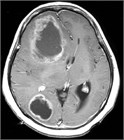

1. JCOG0504試験によって、摘出術後に全脳照射を行う必要はなく、摘出後残存がない場合は経過観察、残存がある場合は定位放射線照射を行うことが標準治療となった。またBrown/Mahajanの臨床試験によると、摘出後に残存がなくとも定位放射線照射を行うことにより、有意に摘出腔の局所制御率が高くなることが報告された(推奨度1)